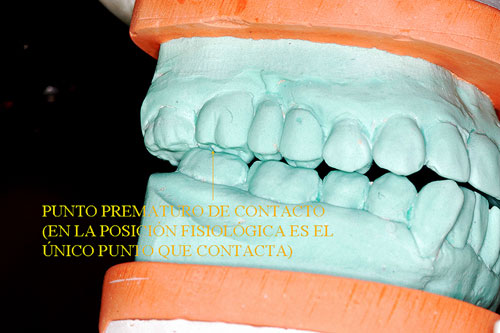

Punto Prematuro de Contacto.(2º Molar Sup. Der.)

En ellos podemos observar múltiples detalles que son difíciles de ver en boca. Podemos ver biotipos, alineación tridimensional, pérdidas de sustancias, etc. Pero sobre todo en los modelos ya montados en ORC (Oclusión en Relación Céntrica), podremos observar las Discrepancias de oclusión entre lo que habitualmente hace el paciente con su mordida y la situación posicional de su ATM, que puede o no coincidir con lo fisiológico y estructural.

En este caso observamos que estando su ATM en Relación Céntrica, al cerrar la boca, solo un punto contacta del lado derecho del enfermo Punto Prematuro de Contacto), lo que hace imposible que con ese único punto desarrolle su función masticatoria y se vea obligado a mover su mandíbula hacia una posición de conveniencia, donde sean muchos más los puntos contactantes que mejoren el desgarro y aplastamiento de los alimentos.

En O.R.C. el Canino no funciona